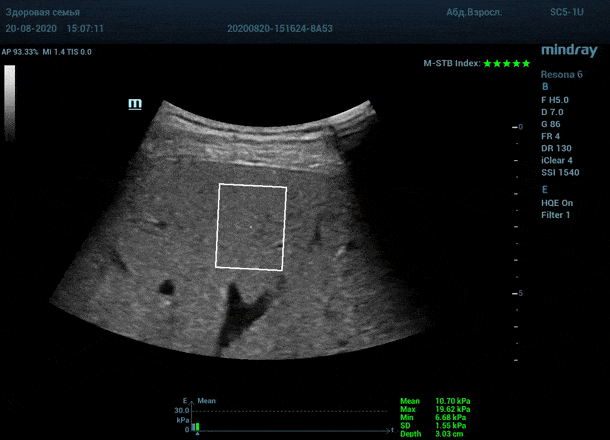

Как работает эластография сдвиговой волны? Датчик посылает плотный пучок ультразвуковых волн в ткани, ткани сжимаются, а затем возвращаются в исходное состояние за счет своей эластичности. Расправление ткани создают поперечные ультразвуковые волны, которые регистрируются трансдьюссером. Прибор во время исследования непрерывно отображает график значений плотности печени (kPa) в исследуемой зоне, достоверным считается график в виде прямой линии. Такая линия формируется путем получения близких по значению показателей. Количественным показателем является отношение межквартального интервала к медиане (IQR/Med). Допустимым считается результат с IQR/Med менее 30%. Чем данный показатель меньше, тем более точным является исследование. Для достоверного исследования в идеале нужно 10 значений.

Для таких сложных случаев в приборах Mindray Resona предусмотрен режим HQ Elasto. В отличии от стандартной работы эластографии HQ Elasto позволяет собрать отдельное короткое измерение в сборный график. Достаточно задержки дыхания всего в пару секунд, показатель будет записан и добавлен в график измерений. Таким образом, короткими «залпами» ультразвуковых волн по печени доктор без проблем соберет все необходимые 10 значений и проведет автоматический анализ с расчетом медианы и IQR/Med.

Приводим видео пример: использованы 3 точки доступа печени, каждое значение графика получено прицельным выстрелом HQ Elasto и собрано в единый тренд. В результате анализа 10 значений получен удивительно точный результат - статистический разброс  3.5 % IQR/Med.